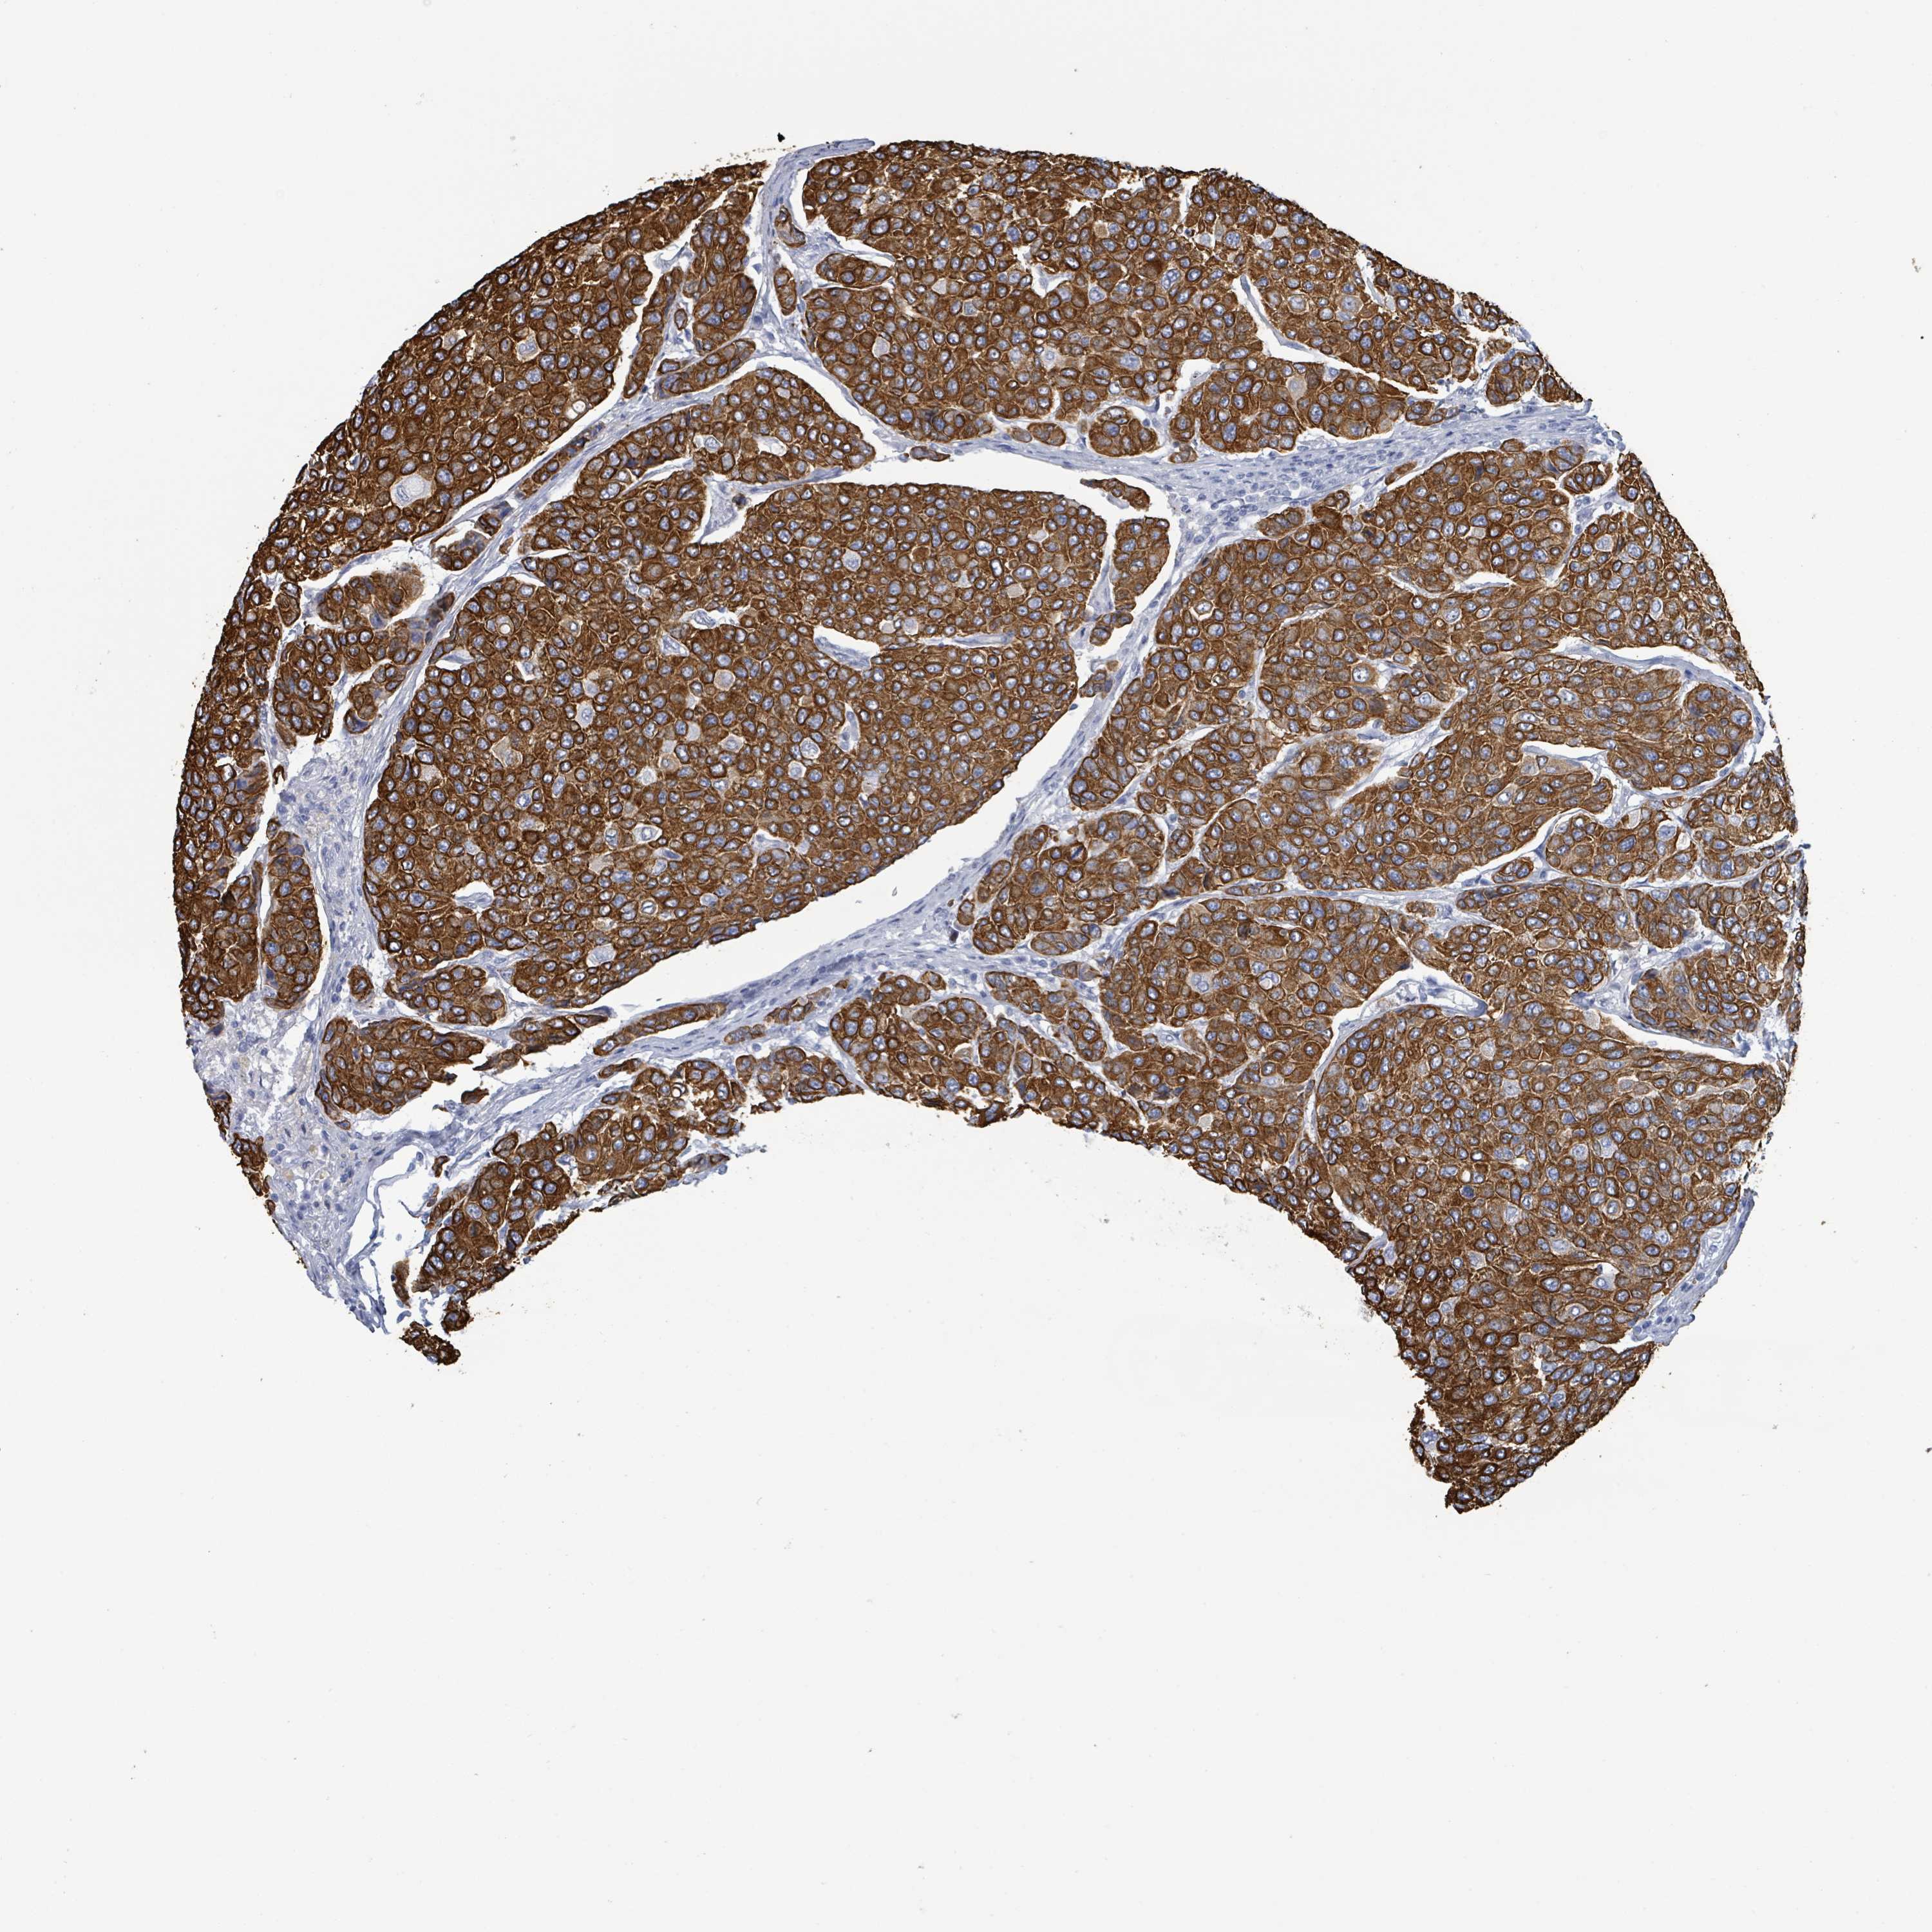

BRCA TCGA BRCA VALIDATION PROTEIN EXPRESSION

Breast cancer

Human cancer